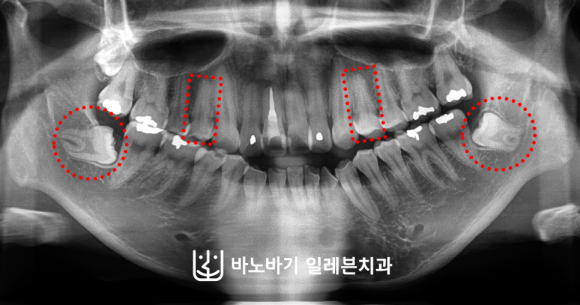

골격 불균형을 보완하기 위해 윗니 양쪽에 위치해 있는 제1소구치 2개를 발거하여 공간을 확보해주었습니다.

하악에서는 옆으로 누워버린 사랑니를 제거하였습니다. 상하로 각각 다른 곳을 뽑는 발치전략을 수립하였습니다.

앞의 여성분과는 다르게 이번 남성분의 경우에서는 교정 이후 따로 수술을 진행하기로 결정하였습니다.

목과 턱선의 경계가 상당히 모호한 것으로 보였습니다. 마찬가지로 호두턱이 관찰되며, 입도 많이 나와 있었습니다.

입이 잘 다물어지지 않고 많이 벌어진 상태였습니다. 이분 또한 입으로 숨을 쉬는 습관을 보이고 계셨습니다.

마찬가지로 상악 두 곳에 발치하여 공간을 만든 다음, 코티코토미 시술로 잇몸뼈를 훨씬 유연한 상태로 만든 후 치아를 훨씬 더 큰 폭으로 움직이는 데에 성공했습니다.

이렇게 하악 총생을 개선하고, 앞니를 조금 더 넣었습니다. 그래서 위와 같이 입술 돌출이 어느 정도는 개선되었습니다.

입을 충분히 자연스럽게 다물 수 있도록 만들었지요. 하지만 측면 안모에서는 변화에 한계가 있었습니다.

그래서 턱끝수술을 받으셨는데요. 아래턱에 볼륨감이 살아나면서 옆모습에 입체감이 생겼습니다.